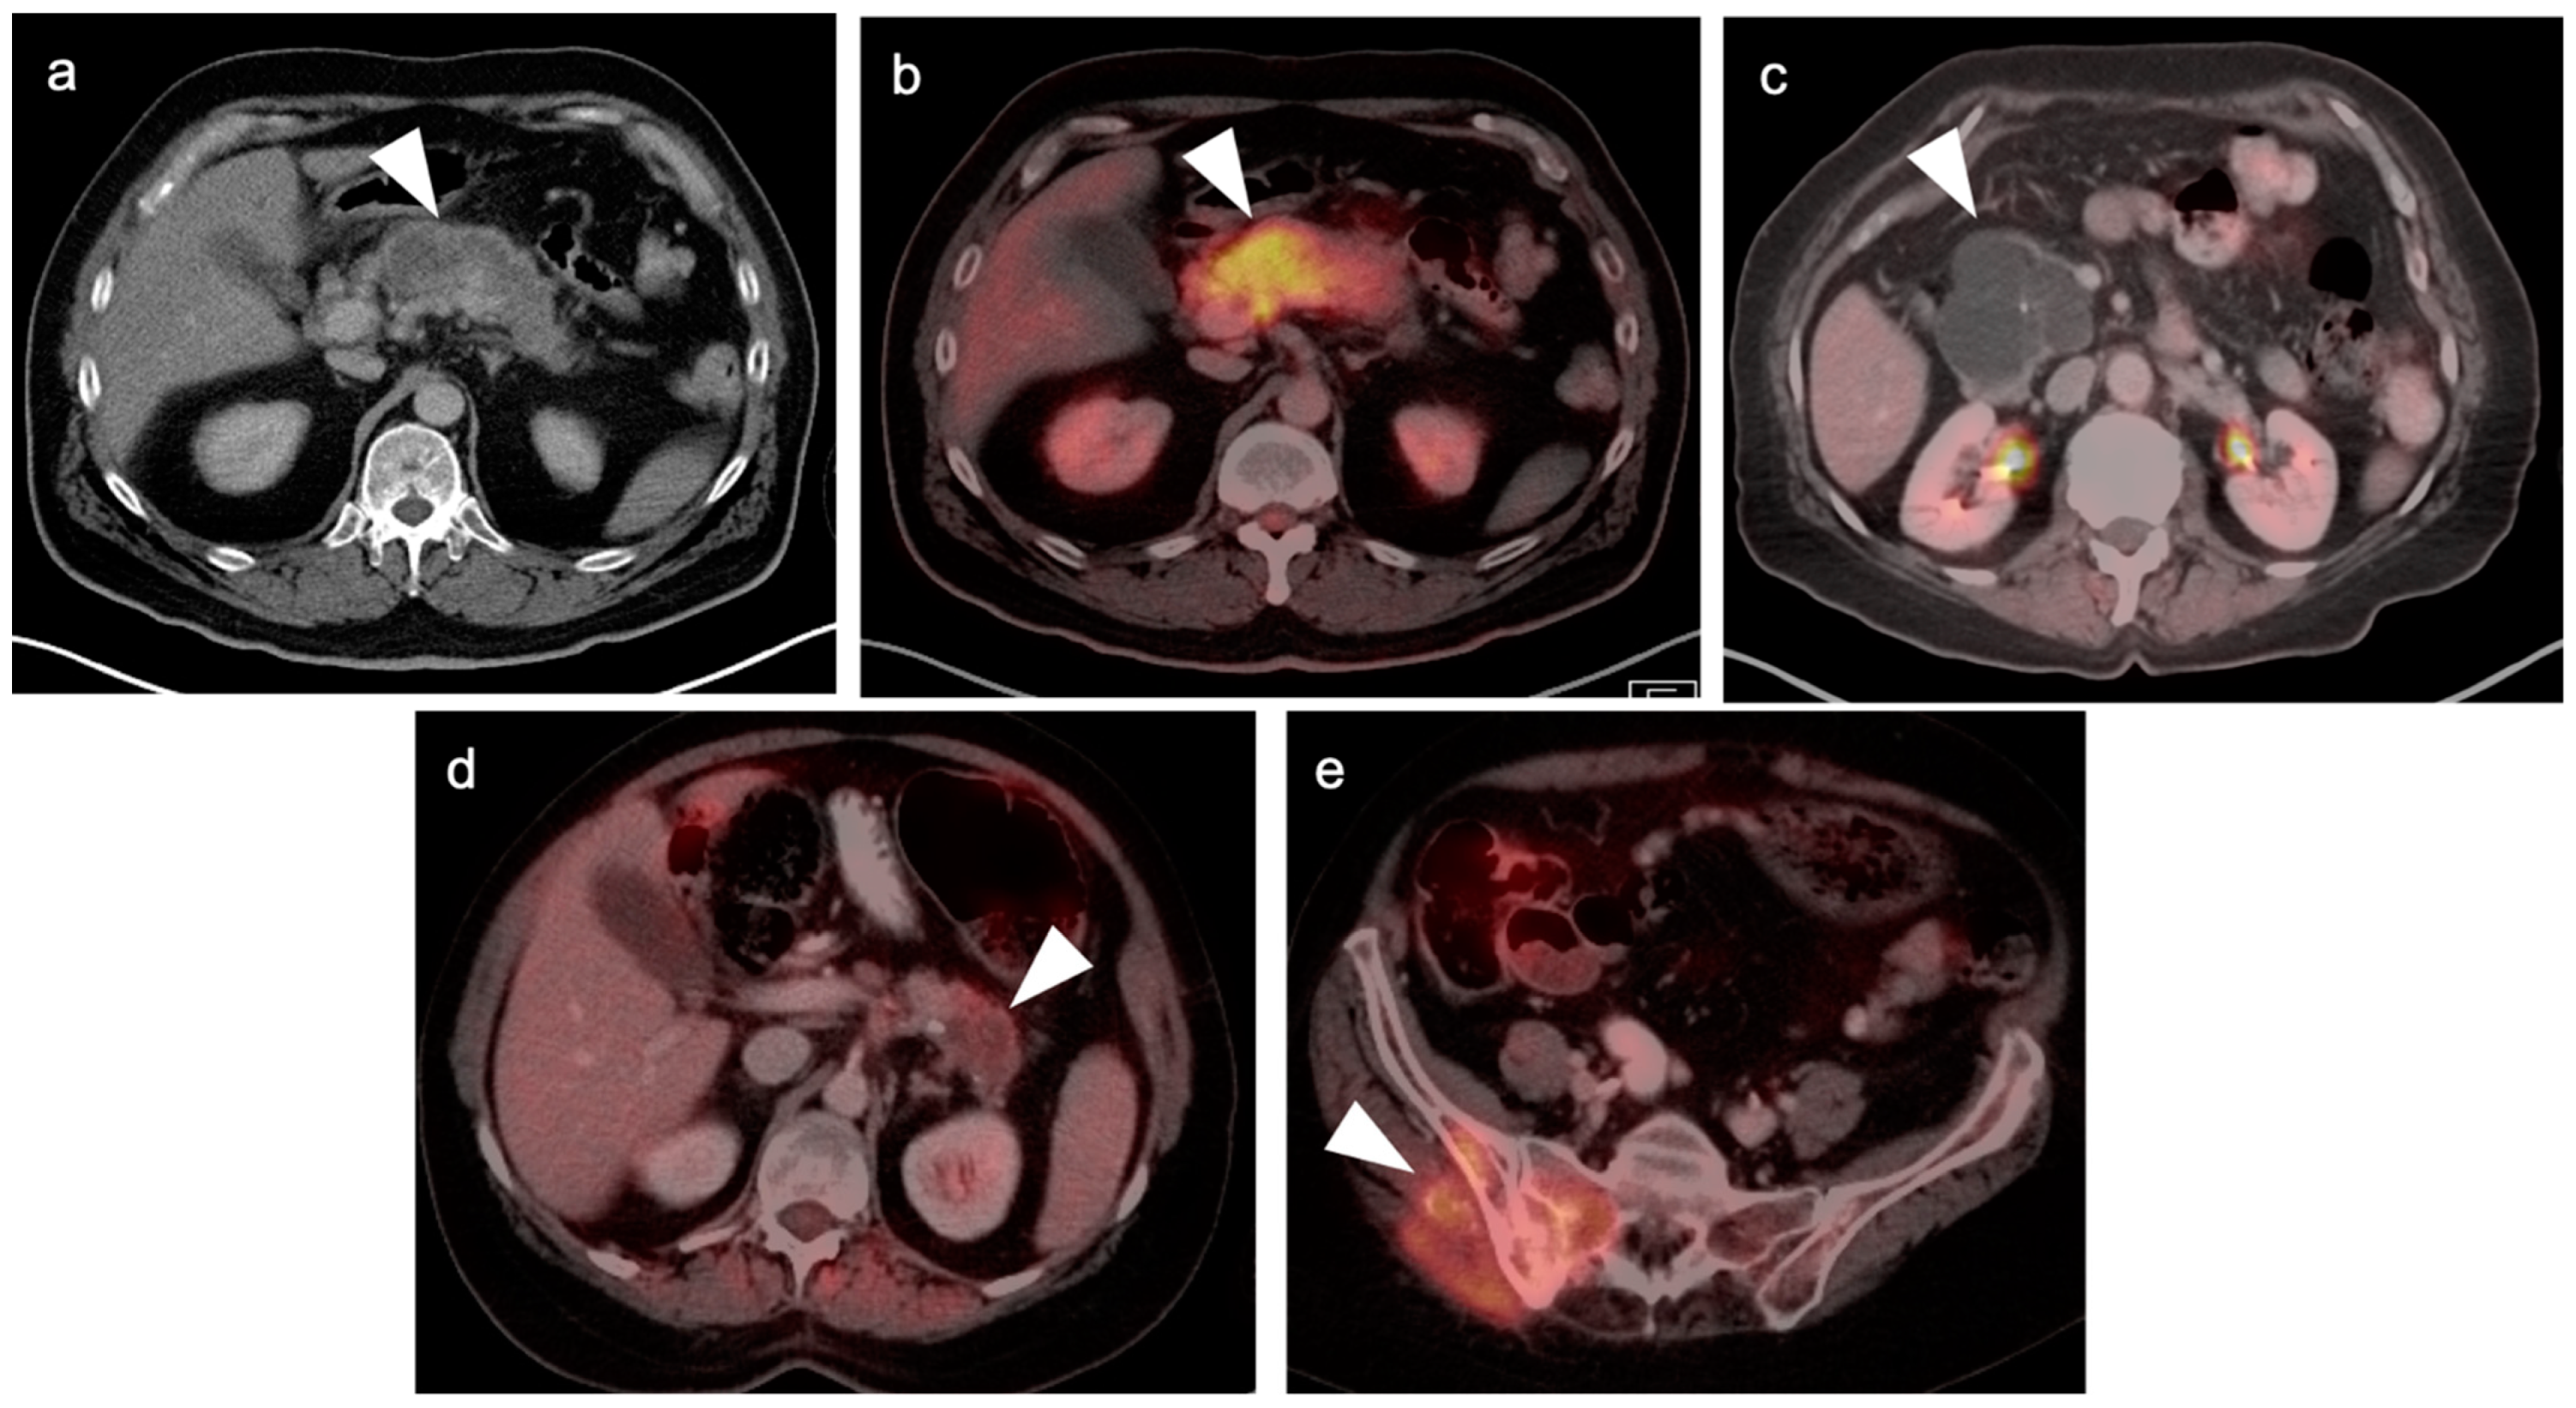

3. Gastrointestinal Stromal Tumor (GIST)